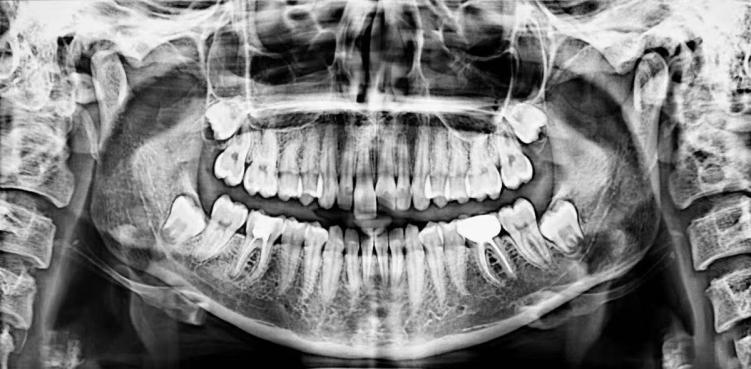

任何成功的手术都始于精密的术前规划。在种植牙领域,锥形束CT(CBCT) 是实现精准规划不可或缺的基石。它彻底告别了传统X光片的“平面猜谜”,能够提供您颌骨的三维立体影像,就好比为医生提供了一份您口腔的“透明地图”或“导航地图”。通过这份高精度的“地图”,医生可以:

精确评估“地基”条件:能够精确测量缺牙区牙槽骨的高度、宽度、密度,就像建筑师勘察土地一样,判断“土壤”是否肥沃坚实,是否满足种植条件,或是否需要先行植骨(“改良土壤”)。

安全规避“地下管线”:能清晰显示下牙槽神经管、上颌窦底、血管等重要解剖结构的位置。术前拍摄CBCT,能够了解口腔神经走向、血管分布、上额窦位置、牙槽骨状况等,是制定安全、精准手术方案的基石。这相当于在施工前就明确了所有地下管线的分布,从而在植入种植体时能够精准避开,极大提升了手术的安全性,从源头上避免了盲目操作可能带来的神经损伤、上颌窦穿孔等风险。